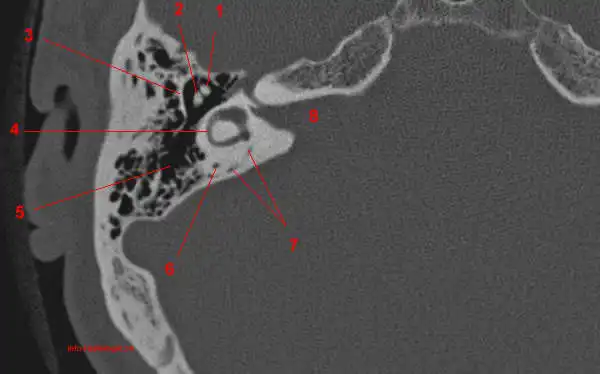

КТ анатомия сосцевидного отростка: особенности и показания